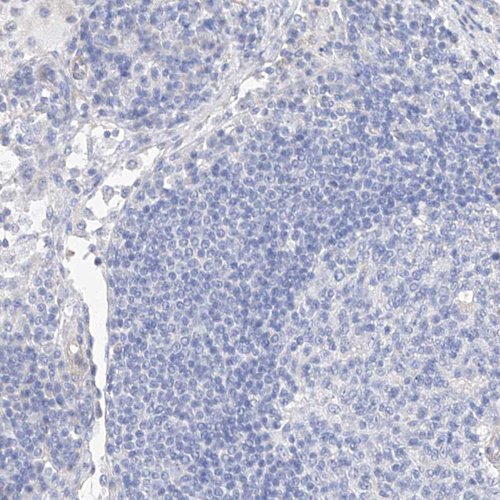

Immunohistochemistry analysis in human cervix, uterine and lymph node tissues using HPA034584 antibody. Corresponding SCGB2A1 RNA-seq data are presented for the same tissues.